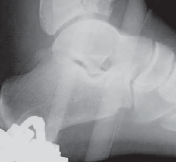

### FIG 3 • Low-energy spiral 43-A type fracture.

24. In contrast to high-energy patterns, rotational injuries ( FIG 3) cause spiral fractures of the distal tibia and fibula originating at the articular level. Intra-articular injury, if present, is typically simple and without comminution or impaction. NATURAL HISTORY